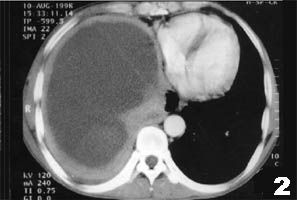

(1)X線胸片:乾性胸膜炎患側僅肋膈角變頓,滲出性胸膜炎中等量以上積液可見大片均勻緻密影,其上緣呈從外上向內下的弧形,肋膈角消失,膈影及心影不清。大量積液時縱膈向健側移位,肋間隙變寬,膈肌下降。

(2)超音波檢查:可了解胸水數量,確定胸腔穿刺部位,鑑別胸腔積液與胸膜肥厚。